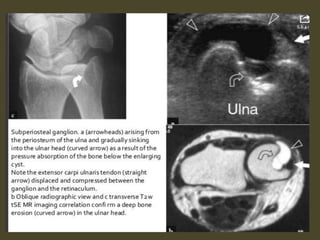

Ganglion cyst.

Tenosynovitis of Extensor Carpi Ulnaris.

Extensor carpi ulnaris tenosynovitis. Axial FS T2-WI shows fragmentation into multiple tendon fragments of

the extensor carpi ulnaris tendon (arrowheads). Note increased fluid and debris within the tendon sheath.